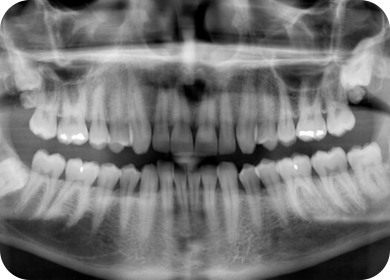

At Shraddha’s Complete Dental Care & Implant Center, we use advanced digital radiology to accurately diagnose dental issues and plan effective treatments. Digital X-rays offer high-quality images with minimal radiation exposure, helping us detect cavities, bone loss, infections, and other oral health problems early—ensuring faster and more precise care.